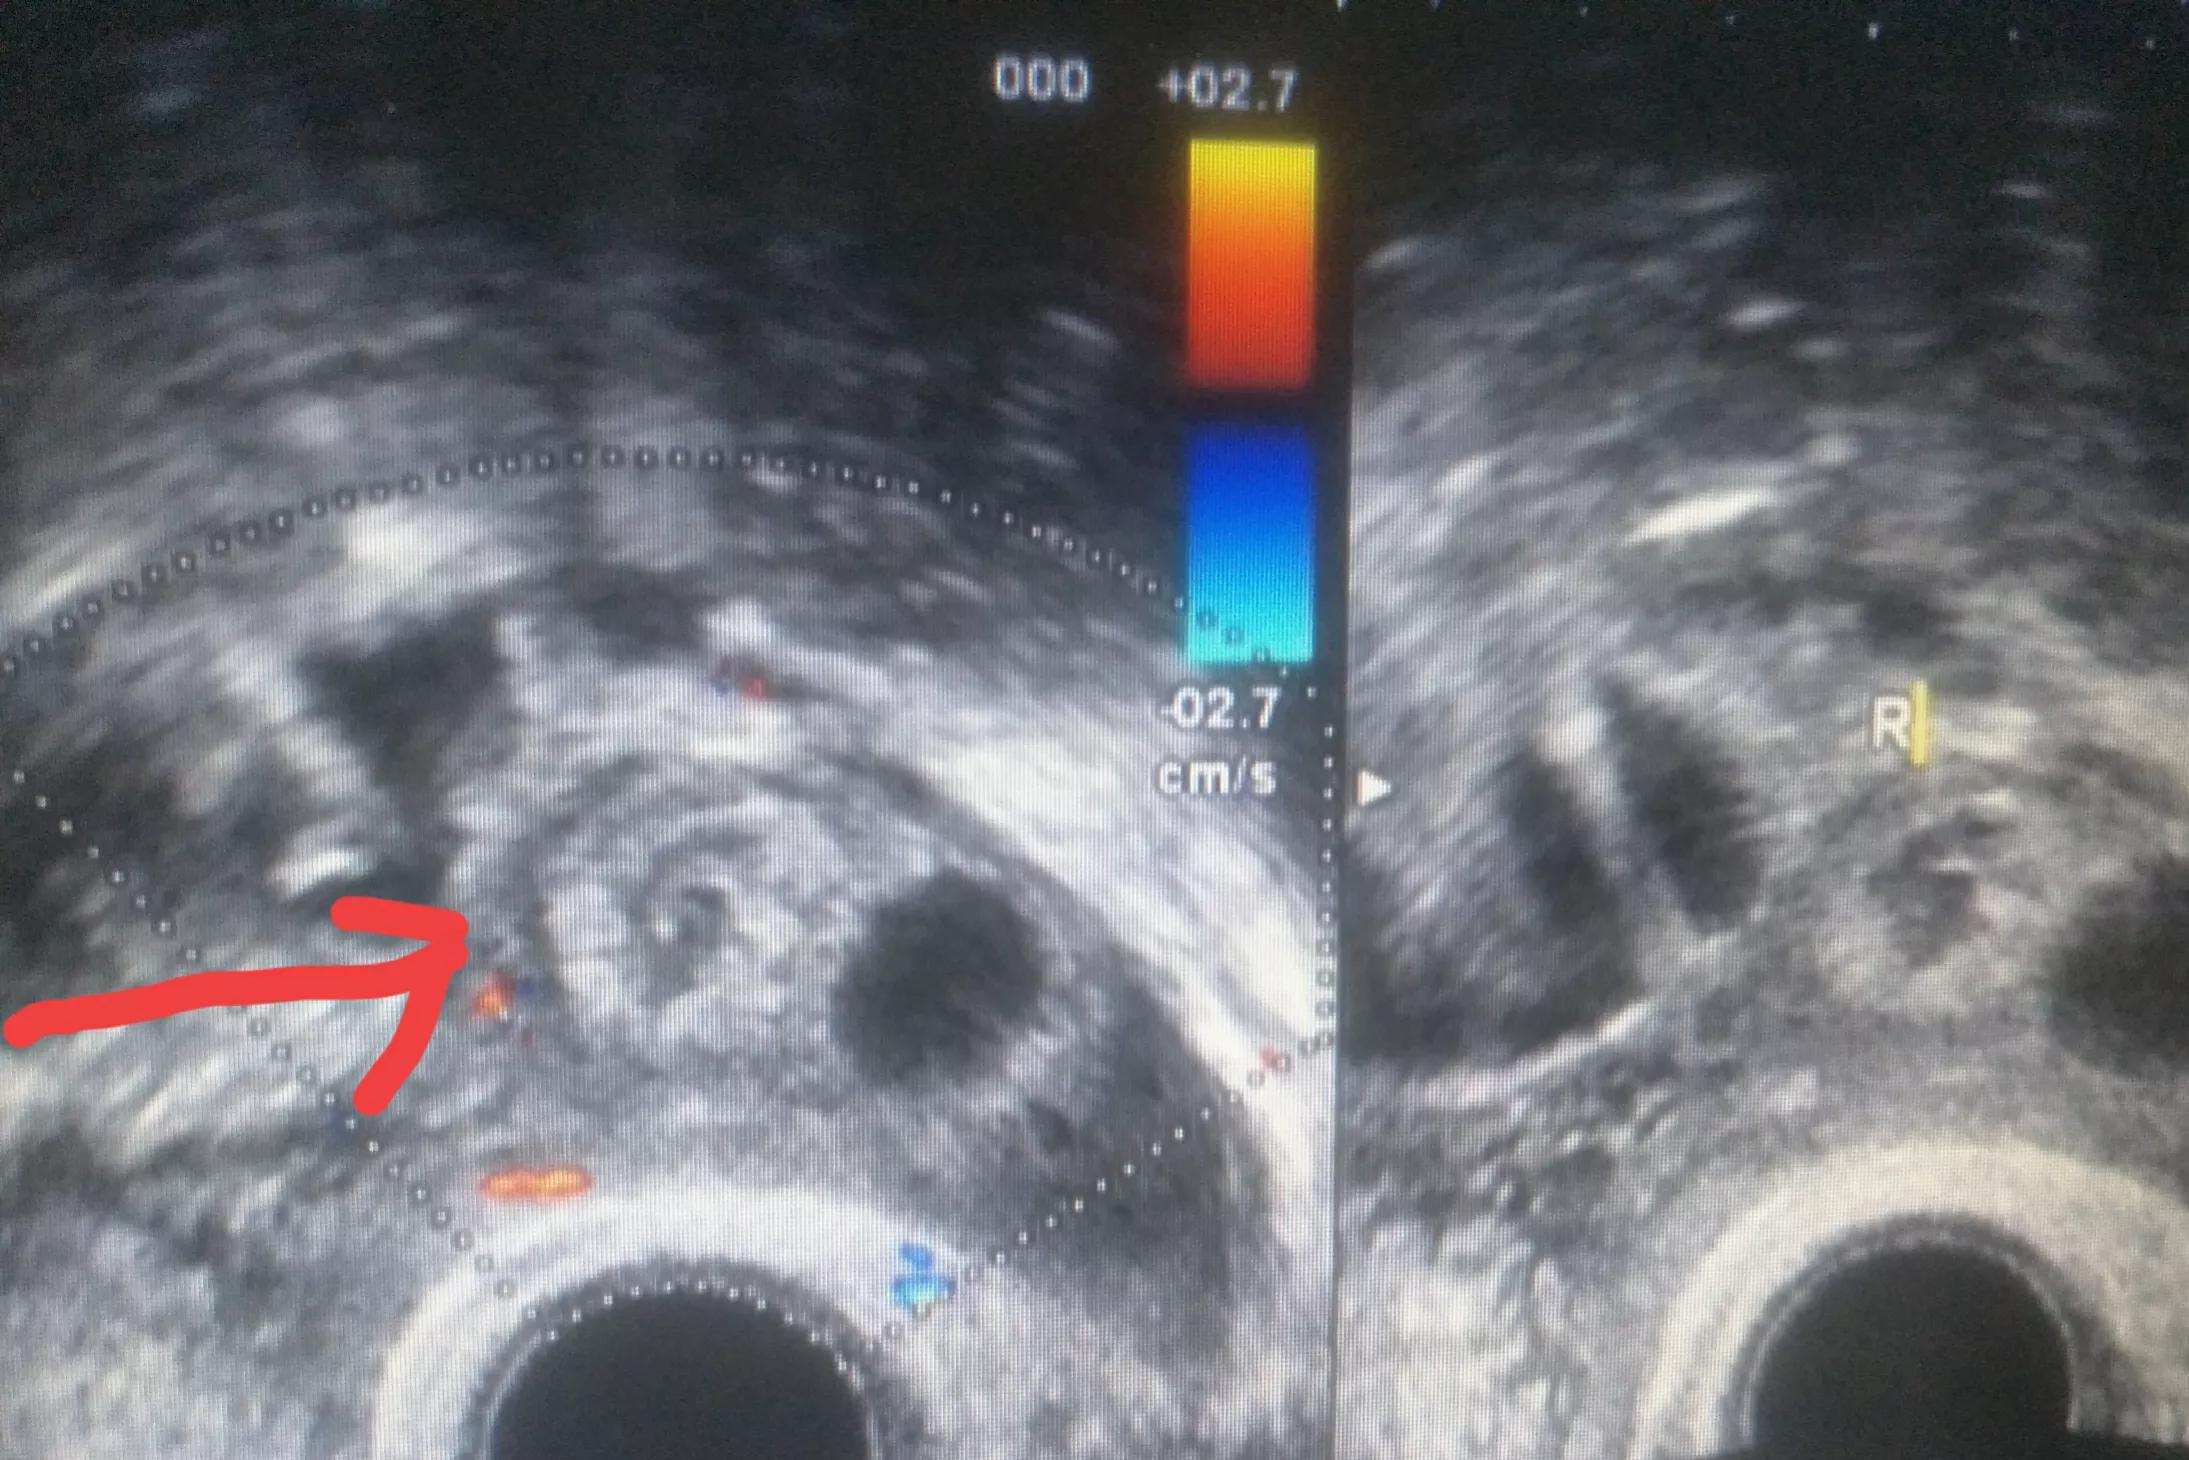

右侧附件区混合性包块(妊娠物)